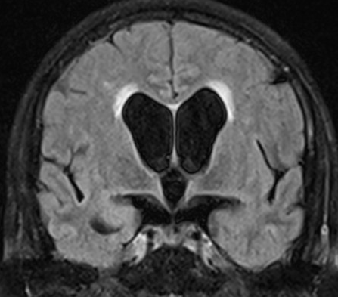

2013-8-2 CT

腰穿脑压240

2013-8-2 MRI